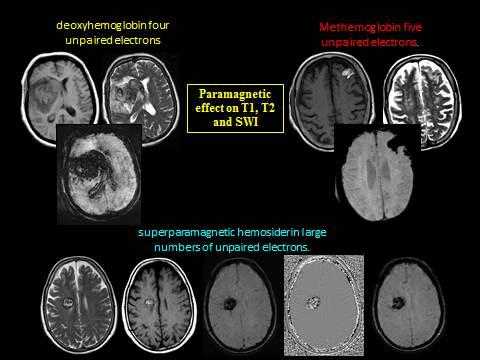

SWI очень чувствительны к кровоизлияниям, кальцию, отложениям железа, медленной венозной крови, и, таким образом, более совершенны, по сравнению с Т2*GRE последовательностями. Потеря сигнала на SWI прямо пропорциональна количеству неспаренных электронов, присутствующих в ткани ( рис. 2 ).

- Визуализация мозговых вен зависит от парамагнитных свойств дезоксигемоглобина, в котором атом железа содержит четыре неспаренных электрона.

- В подострой стадии кровоизлияния, SWI использует парамагнитные свойства метгемоглобина. Атом железа в состоянии окисления содержит пять неспаренных электронов.

- В старых геморрагических поражениях, Т2* деградация сигнала, видимая на SWI, обусловлена суперпарамагнитными свойствами гемосидерина, который содержит большое количество неспаренных электронов.

Рис. 2 Потеря сигнала на SWI прямо пропорциональна количеству неспаренных электронов, присутствующих в ткани.